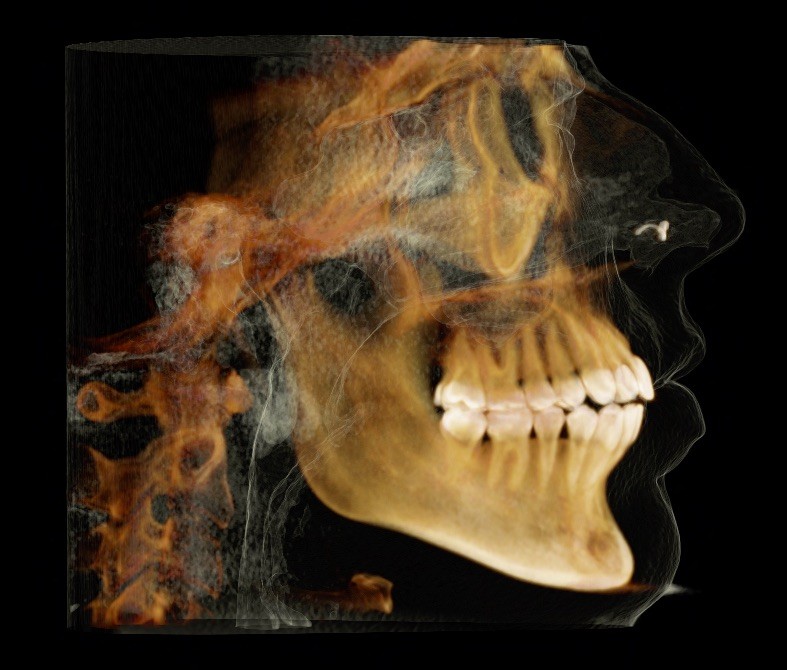

X-RAYS